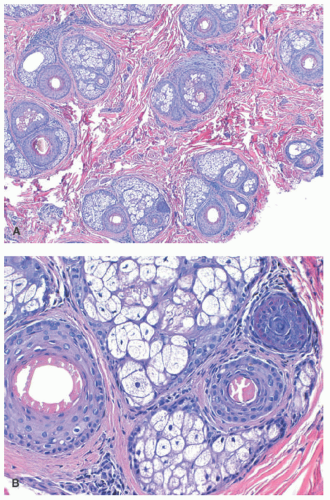

The major histopathologic finding in AGA is miniaturization of hair follicles with a subsequent decrease in the terminal:vellus (T:V) size ratio (Figure 16-2). The normal T:V ratio is approximately 6-8:1,20 but a ratio of 4:1 or less is considered compatible with AGA,21 and a ratio of 2:1 or less is common. Additional findings include a normal overall number of follicles, a slight increase in the percentage of follicles in catagen or telogen phase (up to 20%), and the presence of follicular stelae (fibrous tracts or streamers) underlying the miniaturized hairs.22 In a small study of biopsies of pediatric AGA, 57% showed varying degrees of a lymphocytic perifollicular inflammation and accompanying fibrosis.5 However, inflammation is not a consistent feature, and peribulbar inflammation or associated follicular destruction should be absent. Scarring may occur in longstanding AGA,22 but is unlikely in the pediatric population.

The pathologic changes in AA depend on the stage of disease. In early (acute or subacute) disease, hair counts are normal, but there is a shift to catagen and telogen phases.41,69 Over time, there is a marked decrease in follicular size (Figure 16-4). An infiltrate of lymphocytes around follicular bulbs is a classic, albeit inconsistent finding (Figure 16-4).23 Other diagnostic features are the presence of follicles that either produce minute or no hair shafts, deformed or distorted hair shafts (trichomalacia), lymphocytic exocytosis into follicular epithelium, pigment casts (fragments of displaced pigmented matrix or cortical cells),41 and dilated follicular infundibula plugged with keratin.23

Chronic AA also typically has a normal or near-normal number of follicles,69 with most or all follicles being miniaturized, and a marked shift approaching 100% to catagen and telogen phases. Peribulbar inflammation may be sparse or absent in chronic disease.41 If AA persists for many years, permanent follicular loss may occur.70